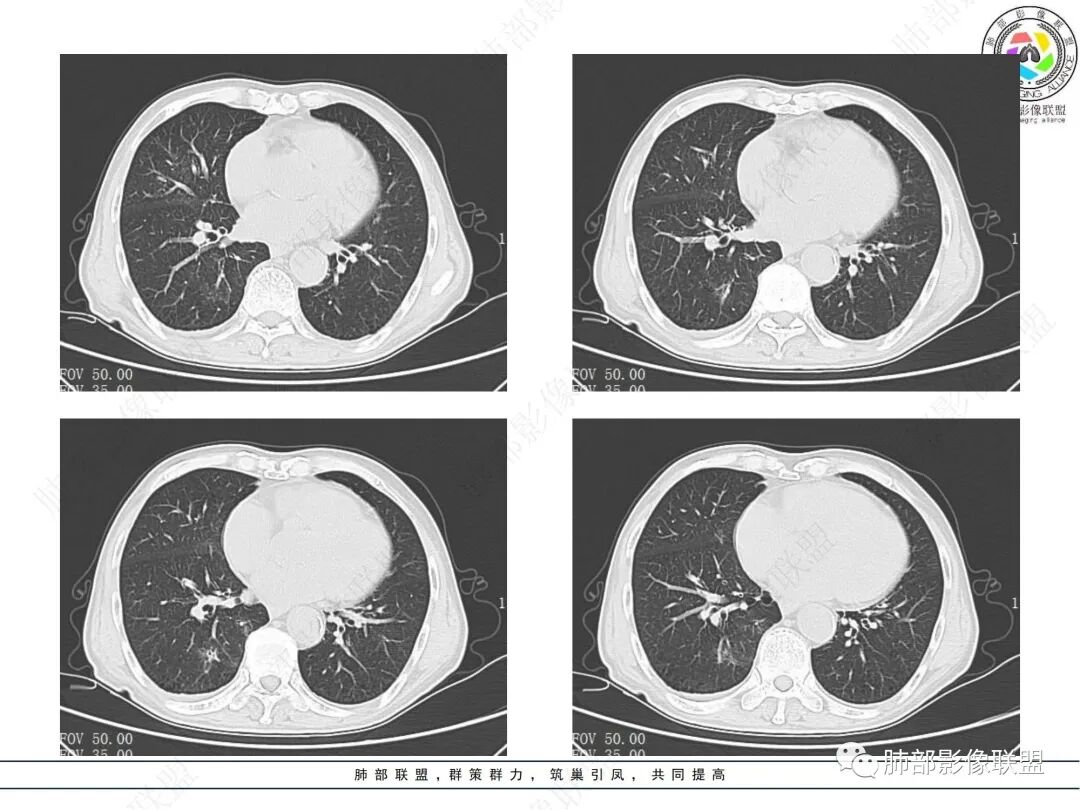

晨读病例,老年男性,乏力,纳差,近来发热,右肺上叶团片状阴影,内见空洞,空洞内壁不光滑,见短液平,增强病灶壁可见不均匀强化,似有边界不清晰的坏死,病灶周围可见片状模糊阴影,考虑恶性病变,鳞癌或腺癌伴感染。

老年男性,肺气肿背景,右肺较大分叶状肿块,密度不均,内坏死空洞形成,坏死区边界不规则,周围多发斑片蜂窝状、网格状高密度影,考虑鳞癌合并感染

右肺上叶及中叶不规则肿块伴周围模糊影,其内小叶间质结节样改变,肿块不均匀强化,坏死及空洞,坏死边界不清,血管显示尚可,考虑腺癌,鉴别淋巴瘤

老年男性,有咳嗽发热。右肺中上叶团状软组织肿块,周围磨玻璃渗出改变,病灶内密度不均,可见低密度坏死及空洞影,空洞内壁凹凸不平,近肺门侧可见明显大面积坏死。近端支气管堵塞不明显。考虑恶性肿瘤伴感染,腺癌?鉴别鳞癌,感染性病变。

右肺上叶团片状阴影,内见空洞,空洞内壁不光滑,偏心,,增强不均匀强化,内有边界不清晰的坏死,病灶周围可见片状模糊阴影,右下肺也有磨玻璃病灶,Crp高,腺癌

70岁男性,发烧病史,右肺巨大肿块,边缘分叶,内部空洞,洞内见附壁结节,局部支气管阻塞,肿块周围见大片阻塞性炎症;实验室检查,炎性指标增高;考虑恶性肿瘤伴阻塞性肺炎,鳞癌可能。

老年男性,乏力,纳差,发热。右肺上叶团片状阴影,密度不均,可见低密度坏死,坏死边界不清,可见空洞形成,见短液平;增强病灶呈不均匀强化,其内血管边缘模糊毛糙;病灶周围可见斑片状渗出病灶,支气管未见明确阻塞。综上考虑肺癌伴感染,鳞癌可能。

老年男性,纳差和发热,炎症指标明显。右肺磨玻璃影伴有肿块,肿块呈膨胀性生长,内部没有气管影。首先考虑感染,并有肿瘤的表现。考虑鳞癌合并感染

右肺上叶实变,密度不均,内可见小气液平,周磨玻璃影,斜裂稍内凹,右下肺可见斑片影,强化可见血管走行自如,右侧胸腔少量积液,考虑感染性病变,努卡?放线菌?

老年男性,肺气肿背景,右肺上叶及中叶大范围实变影,边界不清,支气管通畅,其内见边缘膨隆软组织块影伴不规则坏死、空洞,增强扫描不均匀强化,洞壁显示不清,血管稍变细,实变影内另见多发囊样影,右肺下叶小片状影,病灶跨叶,炎性指标增高,感染应该有的,不除外合并恶性肿瘤(鳞癌?腺癌?)

男,70,反复乏力、纳差20天,发热1天。胸部CT:肺气肿背景,右肺上叶中叶大团片影,实变十磨玻璃渗出。增强实性斑片影内密度不均,可见多发低密度坏死及不规则空洞影,空洞内壁尚光滑,血管边缘模糊。支气管管壁增厚,管腔通畅。右下叶可见小片渗出影。考虑支气管肺炎进展?病原考虑能形成肉芽肿、坏死空洞的微生物,TB?奴卡?鉴别鳞癌。

老年男性,乏力纳差,进食量明显下降,发热,后期少许黄脓痰,无咯血。无胸痛。未提口腔卫生情况,发热时间段不明确,肺气肿背景,气管内痰拴还是其他?觉得是外朝内进展病灶,右肺多叶段病灶,支气管通畅,支气管壁弥漫增厚,实变病灶内有坏死,坏死边界比较清晰,血管破坏不明显,周围散在磨玻璃,边界模糊,无树芽,实变内可疑小钙化,右侧胸水,肺门纵隔淋巴结无明显肿大。病史不太支持化脓菌感染,真菌里隐球强化不太支持,结核需要排除,厌氧菌感染带排,冠状位矢状位病灶觉得类圆形,临床肿瘤也是不能轻易排除的